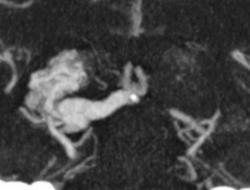

Я чуть увеличил фрагменты изображений с "патологическим состоянием"

Очень наглядна видна сосудистая мальформация.

Питание идет из гипертрофированных задней мозговой и средней мозговой артерий (красные стрелки), дренирование в основном в верхний сагиттальный синус (синий кружок). Дренирующая вена - синие стрелки.